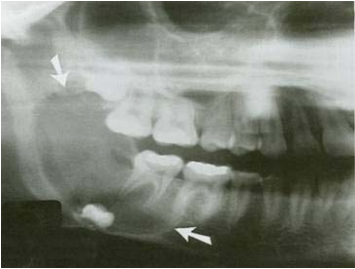

36.一位12歲青少年,無意間發現右臉頰無痛腫脹的情形,經環口放射線影像檢查(panorex),於 右側下顎骨呈現一處多室性病灶(如下圖所示)。有關此例之診斷推論,下列那一項最不合理?

(A)若其右側下齒槽神經支配區域有麻木現象,可以合理懷疑為造釉細胞瘤 (ameloblastoma) (B)以針頭抽吸(needle aspiration)呈現淡黃色清澈液體,可以懷疑為含齒性囊腫(dentigerous cyst) (C)以針頭抽吸(needle aspiration),初期呈淡黃色清澈液體,繼而呈現淡紅色液體,則應可懷 疑是aneurysmal bone cyst (D)由其右側下顎第一大臼齒牙根型態來看,有明顯病理性吸收之現象